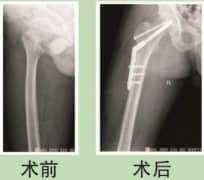

小儿骨折案例分享

小儿骨折后骨折处愈合快、塑性能力强,但有些部位的骨折(如股骨)复位后不容易固定须手术内固定。小儿血液总量很少,需要尽量控制术中出血。下面都没有输血的情况顺利完成手术。 ▲小儿骨折案例分享 : 魏家俊,男,3岁,因被汽车挤压右大腿中段致股骨中段